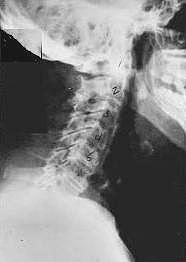

Near Normal

Subluxation Degeneration - Normal This is a side x-ray view of the neck. As with all the pictures you will see on this page, the patient is looking to the right of the screen, so you are viewing the right side of their neck. We will call this picture a "near normal" spine. Compare this spine with the ones you will see below on this page. Notice the normal forward curve of the neck. This curve helps absorb shock. Notice how each of the disc spaces between C2 (second bone in neck) and C7 are thick and even, this again is normal. Also notice how the front portions (right on the x-ray) of each of the vertebrae (called the 'body' of the vertebrae) are fairly square with clear and well defined borders. This type of arrangement is normal in the neck. Normal vertebrae in other parts of the spine also have similar characteristics to what we see here. When subluxations occur and are left uncorrected, ongoing relentless changes occur that result in damage to the structure and function of the spine along with nerve damage and the resulting problems caused from improper nerve supply.